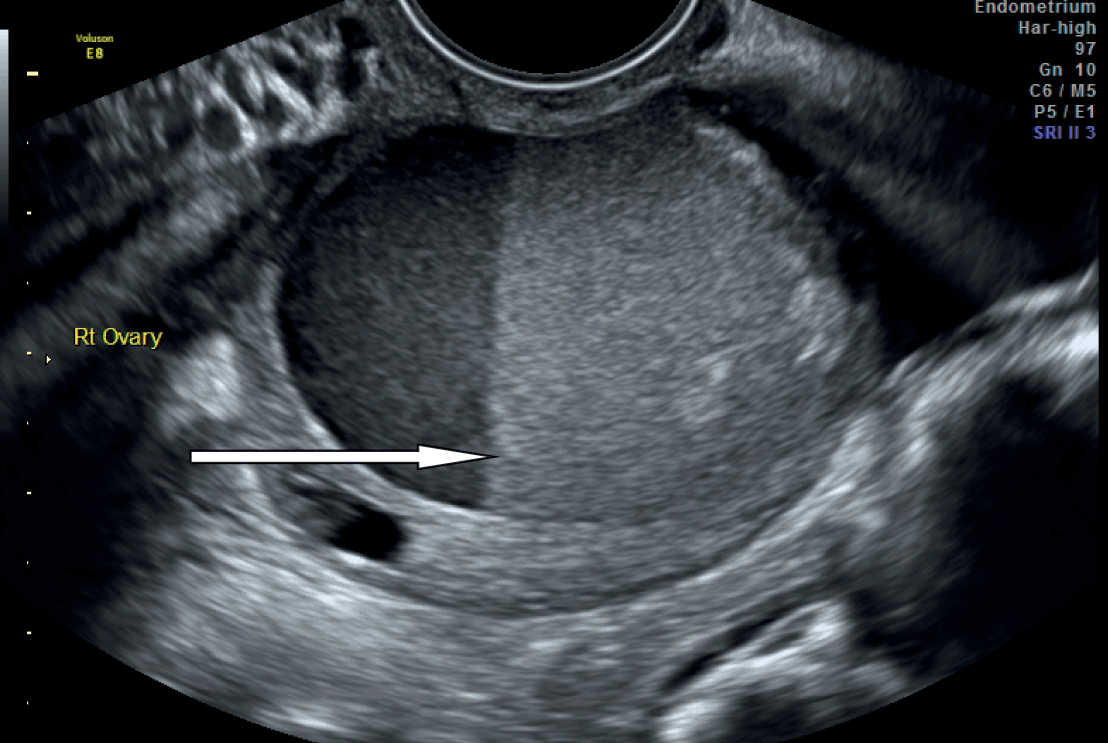

Describe the Image (use ultrasound terminology)

Fluid Fluid level